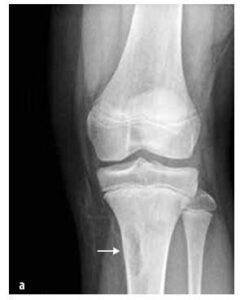

Acestea apar mai frecvent la copii decât cele maligne, de exemplu tumori osoase (osteom osteoid, osteoblastom, granulom eozinofilic), ligamentare (displazie fibroasă, fibrom neosificat (vezi imaginea nr. 7)), chisturi osoase, cartilaginoase (osteocondrom, encondrom, condroblastom) și altele (hemangiom sinovial și sinovită vilonodulară pigmentară).

Imaginea nr. 7

Fibrom osos neosificat